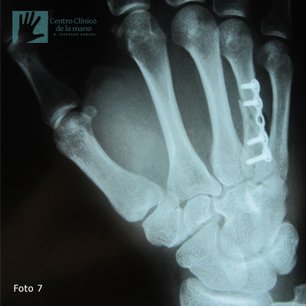

Fractura del Metacarpiano